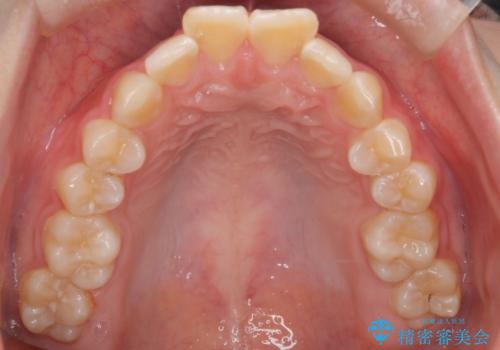

- 前歯が出ていることを主訴に来院されました。

インビザラインにて奥歯の遠心移動を行いながら最大限前歯が下がるように治療を行いました。

今回は遠心移動とIPRによってここまで前歯を下げることができました。